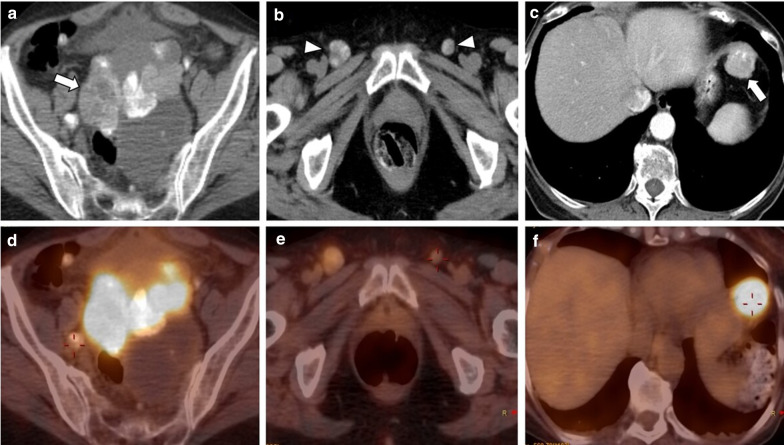

Fig. 8.

Local recurrence of LGSC with peritoneal and lymph node metastases in a 74-year-old female. Axial unenhanced CT images display a large, heterogeneous, mixed tumour in the vaginal dome (arrow) (a) with bilateral inguinal lymph node metastases (arrowheads) (b), both with calcified psammoma bodies. Axial enhanced CT image reveals a peritoneal metastasis in the left hypochondrium peritoneum (arrow) (c). FDG-PET/CT images show a hypermetabolic pelvic lesion (d), bilateral inguinal lymphadenopathies (e) and a left upper hypochondrium peritoneal lesion (f), suggestive of malignancy

Positron emission tomography (PET)/CT

Fluoro-2-deoxy-d-glucose (FDG) PET/CT has a limited role in the primary diagnosis of adnexal masses since false-negative findings have been detected with borderline tumours, mucinous tumours, and other low-grade types of tumours. False-positive results have also been reported with bowel loops, follicular cysts, corpus luteum cysts, and in some benign ovarian tumours [1, 2, 10, 15]. Yet, despite this, FDG-PET/CT can help diagnose and stage advanced disease (stage IV disease), specially when CT is indeterminate [1, 13, 15]. FDG-PET/CT metabolic activity provides disease detection in small metastases or lymph nodes, which can be difficult to characterise only with CT [13, 15] (Fig. 8).

Recently, FDG-PET/CT has revealed similar or higher sensitivity (95–97%) and specificity (80–100%) than CT or PET alone to detect recurrent or residual disease [1, 15, 23].

The identification of metabolic activity in infracentimetric metastases and the detection of disease between intestinal loops, especially after surgery, are recognised limitations of PET [1, 15]. Despite this, the anatomical resolution and metabolic activity of FDG-PET/CT outperform those of CT and MRI in detecting lymph nodes recurrent disease and unresectable sites [1, 15].